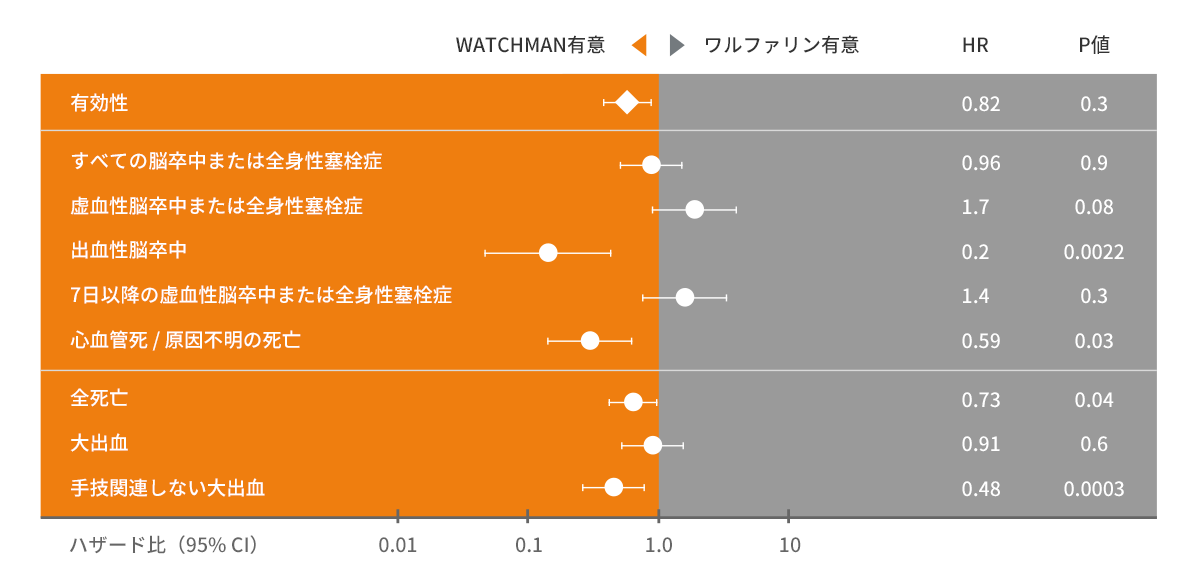

WATCHMANとワルファリンの効果を比較

WATCHMANは、出血などでワルファリンを長期間服用できない非弁膜症性心房細動患者さんに対して、ワルファリンと同等の有効性を示唆する結果が示されました。WATCHMANはそのような患者さんに対する代替療法です。

WATCHMANを留置することで、ワルファリン投与を中止することができます。2つのランダム化試験のメタ解析でWATCHMANとワルファリンの効果を比較しています。

WATCHMAN 臨床試験で確認されたこと

WATCHMANは、多くの臨床研究(PROTECT AF、CAP レジストリー、PREVAIL、CAP 2 レジストリー)から長期成績などのエビデンスが得られています。

承認後の分析において、WATCHMANは長期的なワルファリン治療の代替療法として、ワルファリンを長期間服用できない非弁膜症性心房細動患者に対して手技成功率の高さと合併症発生率の低さを示唆する結果が示されました。多くの試験が行われてきたWATCHMANの安全性および有効性が、長期臨床成績によって評価されました。